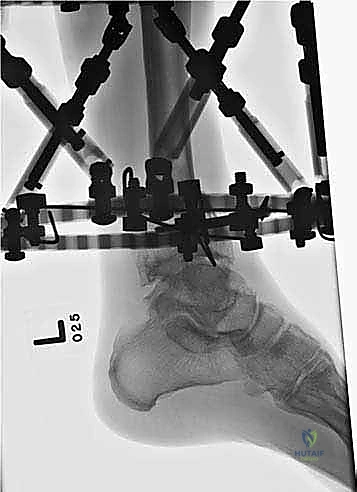

المرحلة الثانية: تركيب المثبت الخارجي (Frame Application)

قبل قطع العظم، يقوم الدكتور هطيف بتركيب الهيكل الخارجي (الإليزاروف أو الفريم الدائري).

1. يتم إدخال أسلاك دقيقة جداً (K-wires) ومسامير نصفية (Half-pins) عبر الجلد إلى العظم بدقة متناهية لتجنب الأعصاب والأوعية الدموية.

2. يتم تثبيت هذه الأسلاك في الحلقات المعدنية الخارجية. حلقة أو حلقتين فوق مكان القطع المخطط له، وحلقة تحته (في الجزء السفلي من الساق والقدم إذا لزم الأمر).

3. يتم التأكد من استقرار الهيكل الخارجي بالكامل.

المرحلة الثالثة: قطع عظمة الشظية (Fibular Osteotomy)

للسماح للظنبوب (العظمة الرئيسية) بالتحرك والتصحيح، يجب أولاً قطع عظمة الشظية. يتم ذلك عبر شق جراحي صغير جداً (حوالي 1-2 سم) في الثلث السفلي أو الأوسط من الساق.

المرحلة الرابعة: قطع العظم عبر الجلد (Percutaneous Tibial Osteotomy)

هنا تتجلى مهارة الجراحة بأقل تدخل:

1. يُجري الدكتور هطيف